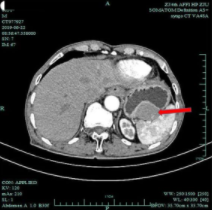

2019年

这次因为腹部剧痛送诊后,专家发现,金大伯的肿瘤已经大了一倍,生长至近 10 公分大小,已经破裂出血。